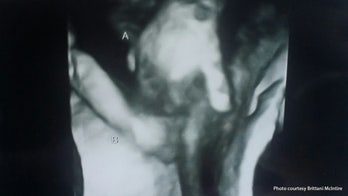

February 18, 2016 Heartbreaking sonogram image depicts dying twin holding sister's hand Doctors expect only one of Brittani McIntire’s twins to survive, but the Kansas mom said she is grateful her baby won’t pass away without someone holding his hand.